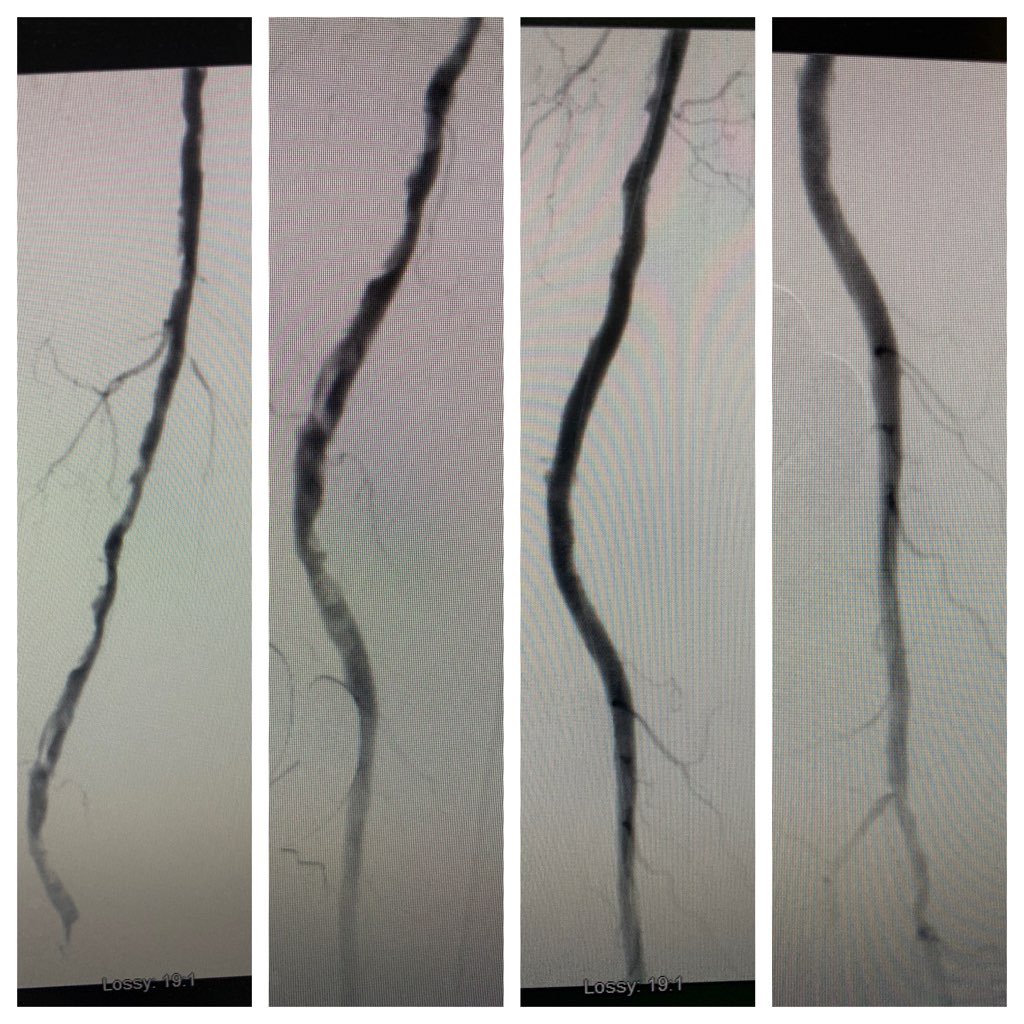

72 yo M offered amputation after failed attempt at crossing CTO at another facility.  Femoral endarterectomy with antegrade and pedal access for through and through wire access, angioplasty/stent.  Now post op one month, wounds healing, abi from 0.2 to now 0.88.

74 yo w non healing wound of several months duration.  Long segment cto with no vein.  Antegrade and retrograde via the pt, through and through wire access with eventual supera placement.  Now wound healed on 3 month follow up.